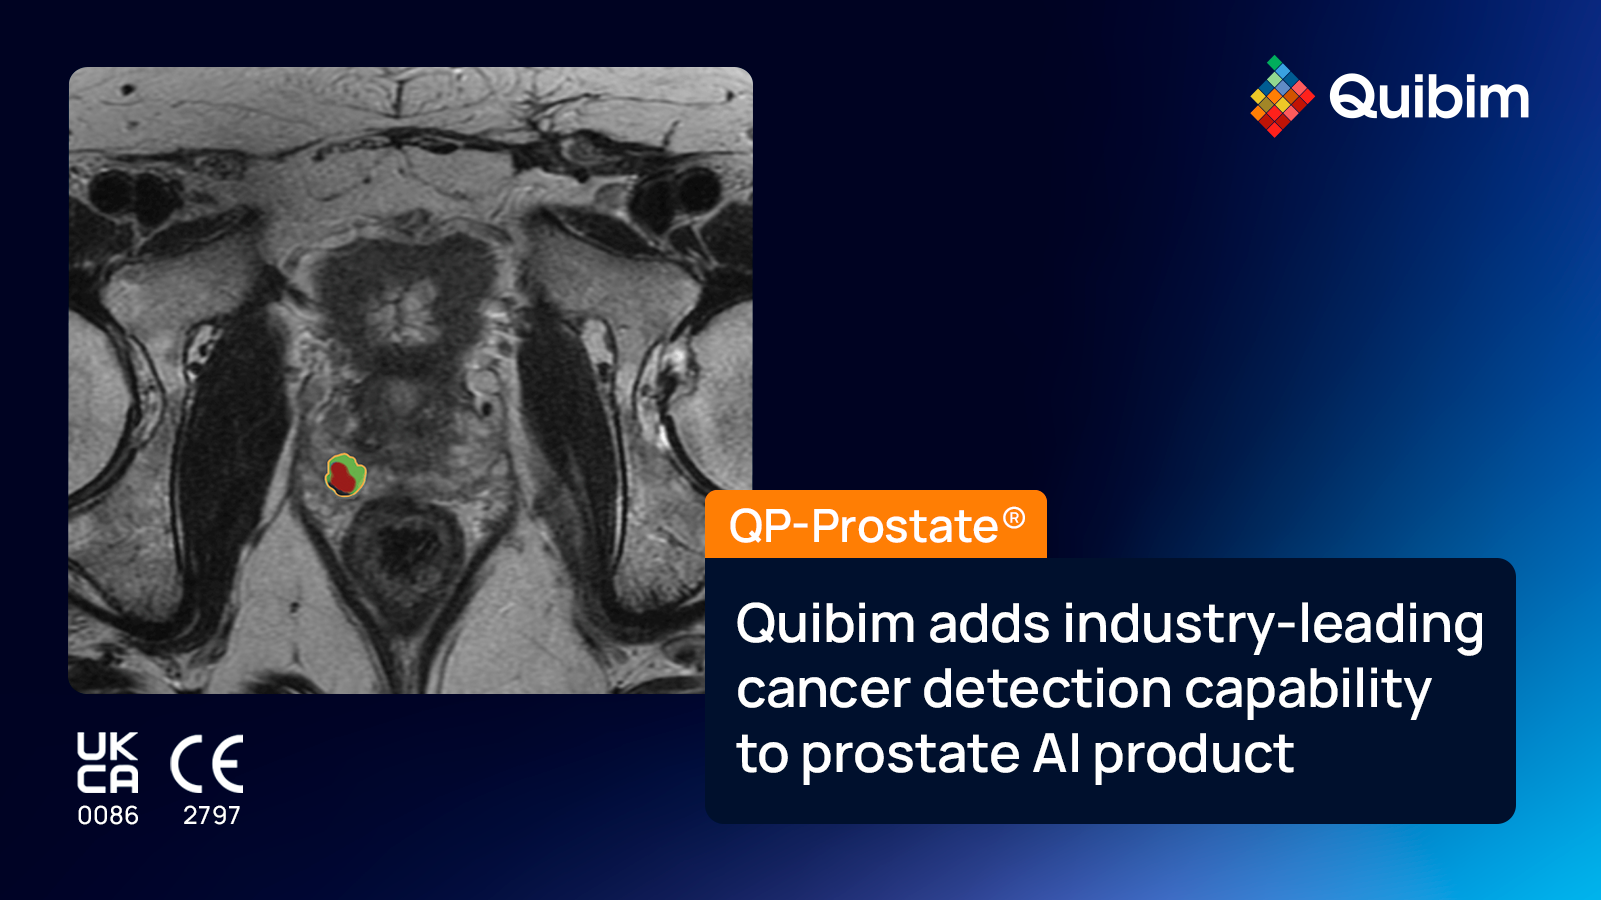

AI-driven organ/lesion segmentation

Organ-agnostic automated methodology for model development applied to various imaging modalities (MRI, CT, PET, PET/CT, PET/MRI), anatomical areas and clinical conditions, combined with an innovative procedure for quality checks and anomaly detection.

AI-powered based-imaging tools

The AI Radiomics analysis modules help our customers go one step further in their research by revealing information embedded within conventional scans for various anatomical areas, increasing the diagnostic accuracy, prognostic evaluation, and prediction of therapeutic responses.